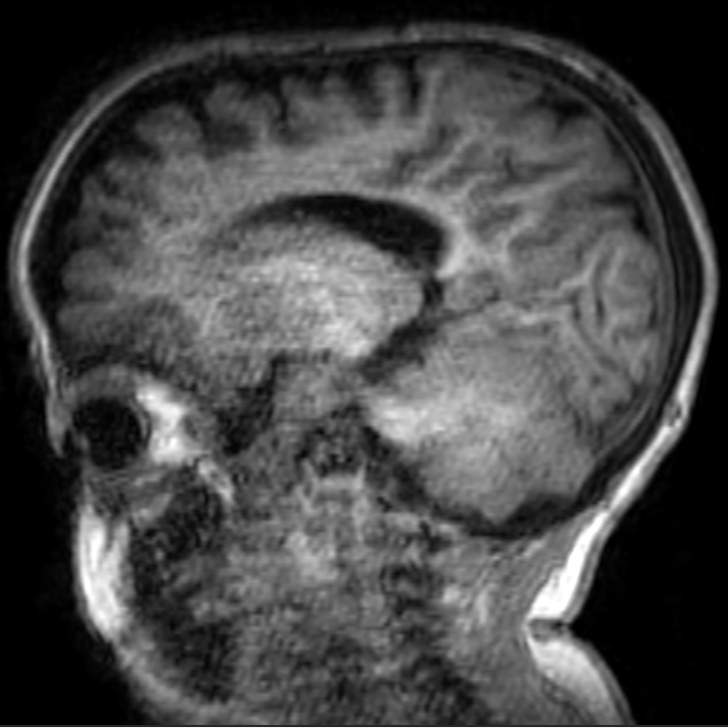

黏多糖贮积症,头颅核磁共振矢状面,颅骨呈“舟状头”,伴脑萎缩